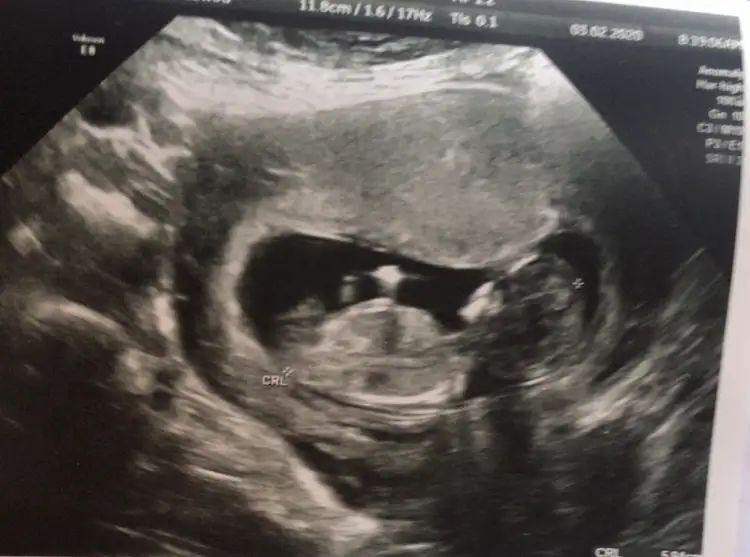

1 usg daha varsa paylaşınTeşekkürler tahminler için12+4 günlük bugün ikili testte doktor yanilabilirim ama kız dedi emin olmayınca ben de tahminleri merak etmiştim. Bakalım ilerleyen haftalarda ne olacak

Aaaa hayırlısı olsun Hepimiz erkek demişiz netleşince yaz bize deTeşekkürler tahminler için❤ 12+4 günlük bugün ikili testte doktor yanilabilirim ama kız dedi emin olmayınca ben de tahminleri merak etmiştim. Bakalım ilerleyen haftalarda ne olacak☺

kız galiba? bakalım ne kadar anlıyorum bende12+4 dktor %80 ihtimalle cinsiyet tahmn rtti ama emin olamadık. Sizin tahmininizi merak ediyoruz

Erkek gibi nubu tam dik değil ama paralelde değil oyum erkek kullanıyorum12+4 dktor %80 ihtimalle cinsiyet tahmn rtti ama emin olamadık. Sizin tahmininizi merak ediyoruz